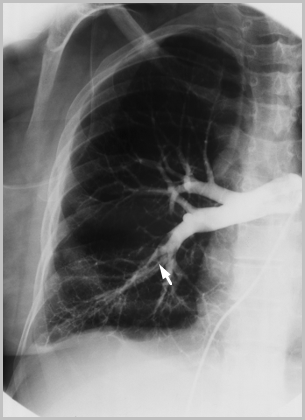

EMBOLIA PULMONAR

ARTERIOGRAFIA PULMONAR

Defectos intraluminales de llenado